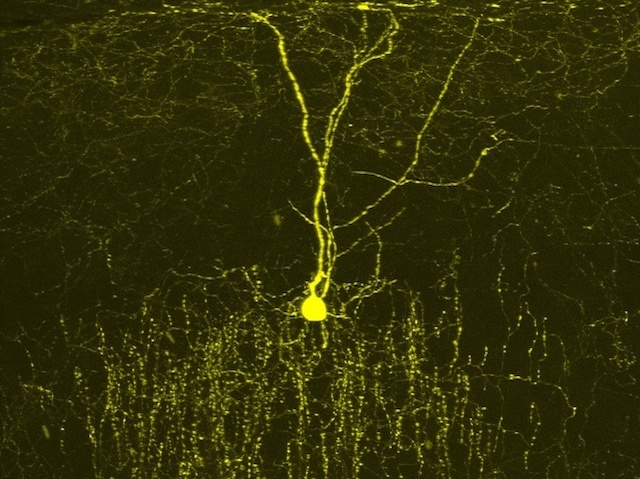

Excessive Inhibition

People with Down syndrome have three copies of chromosome 21 instead of two, meaning an extra copy of each of the 250 or so genes on the chromosome. Figuring out which are responsible for the various issues associated with Down syndrome is challenging. But scientists have recently determined that the gene encoding DSCAM – a cell adhesion molecule involved in neuronal circuitry – is a likely cause of at least some of the neurological symptoms. Studies in mice with simulated Down syndrome revealed an extra copy of DSCAM caused chandelier cells (like the one pictured) to develop more axons. Chandelier cells are inhibitory neurons and naturally have large numbers of axons – their branching shape giving the cell its name – but extra DSCAM caused even more axonal connections with target cells and thus greater inhibitory activity. Further work may reveal how this inhibition leads to neurological symptoms and whether it can be modulated.